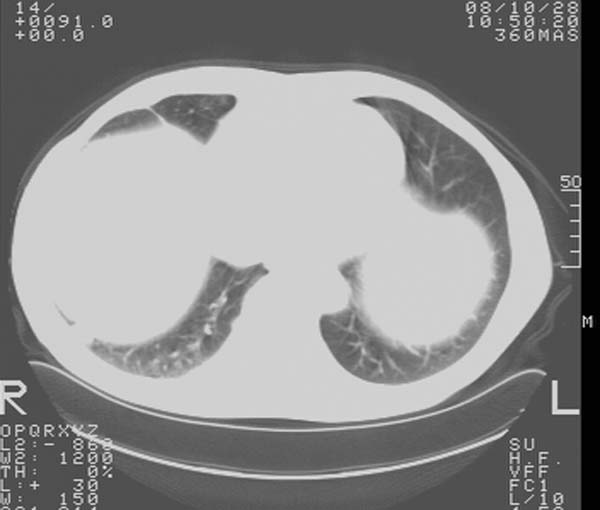

m,65y。半年前发现颈小结节,逐渐增多增大,现双侧耳后、颌下及颈部表浅淋巴肿大。胸片示双肺门增大。外院曾穿刺诊断为淋巴结核。在我科作胸腹部ct,我们觉得外院病检有误。现将图像上传请战友讨论。

纵隔内及腹膜后广泛淋巴结肿大,脾大,肝内似可见低密度影,结合病史半年前发现颈小结节,逐渐增多增大,现双侧耳后、颌下及颈部表浅淋巴肿大。考虑淋巴瘤。

纵隔,双肺门腹膜后多发淋巴结重大,非融合,肝脾轻度肿大,双肺野弥漫性小结节;考虑淋巴瘤,结节病可能性

纵隔内,双肺门、腋窝及腹膜后多发肿大淋巴结影,肺内小结节影,肝脾体积增大,支持淋巴瘤。肝内多发低密度影,考虑小囊肿。

考虑淋巴瘤肺、肝内转移,脾脏肿大。

纵隔内,双肺门、腹膜后多发肿大淋巴结影及颈部淋巴结肿大,肝脾体积大.结合临床,淋巴瘤可能性大。